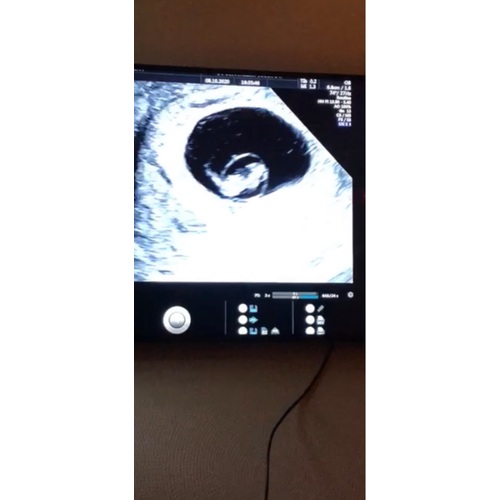

De baby zit in een vruchtzak met amnion en chorionvliezen eromheen. Als de baby groeit en er meer vruchtwater bij komt groeien de vliezen tegen de randen van de baarmoeder en placenta aan en zie je ze dus niet meer. Dit zijn ook de vliezen die uiteindelijk breken als je moet bevallen.

Hier ook zichtbaar en opvallend straks bij 8 weken, dus een extra echo gehad met 12 weken, toen al mooi verruimd en ‘flubberig’ waardoor de kans op scheuren veel minder was. Normaal trekt dat Amnionvlies vanzelf in de eerste weken richting de vruchtzak, soms dus alleen een beetje trager. Het enige risico als dat traag of niet gebeurt - voor zover ik begrepen heb - is dat het kan scheuren en strengen kan vormen die bijvoorbeeld vingertjes kunnen afknellen. Vandaar dat ‘flubberig’ volgens de echoscopiste een heel goed teken was ;-)